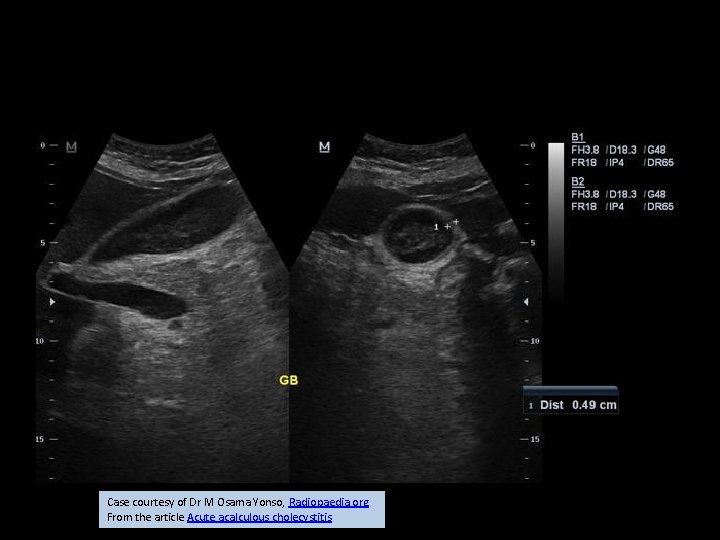

Case courtesy of Dr M Osama Yonso, Radiopaedia. org. From the article Acute acalculous cholecystitis

calculous cholecystitis

Radiologic signs • • Approximately 90 -95% of cases are due to calculus obstruction of the gallbladder neck or cystic duct, leading to increased intraluminal pressure and distention. Inflammation may result from chemical injury of the mucosa by bile salts and/or superimposed infection. Ultrasound (US) is the preferred initial modality in the investigation of right upper quadrant pain. It is more sensitive than HIDA scintigraphy 4 and CT in the diagnosis of acute cholecystitis, and more readily available. The most sensitive US finding in acute cholecystitis is the presence of cholelithiasis in combination with the ecographic murphy sign. Both gallbladder wall thickening (>3 mm) and pericholecystic fluid are secondary findings. Other less specific findings include gallbladder distension and sludge. Every effort should be made to demonstrate the obstructing stone in the gallbladder neck or cystic duct.